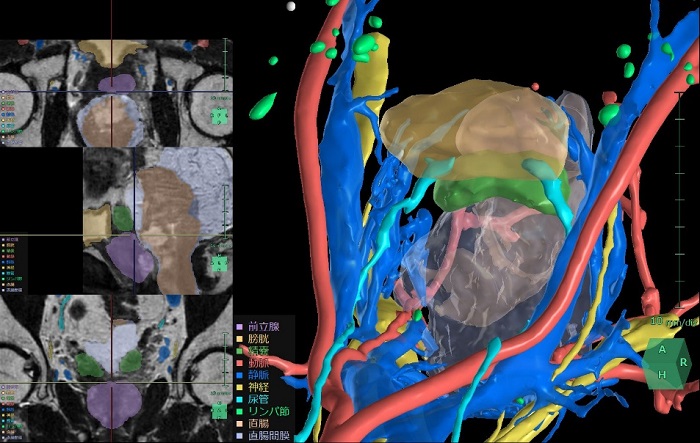

「SYNAPSE VINCENT Ver7.3」の婦人科臓器解析の解析画面

「膀胱周辺臓器解析」は、術前のCT画像やMR画像から3D構築を行うことで、骨盤腔(こう)内のぼうこう周辺臓器や神経、血管の位置関係を把握し、患者ごとに異なる血管走行などの解剖学的特徴を確認し、手術シミュレーションを行うことができる。機能がぼうこう周囲の臓器や神経、血管の位置把握を支援することで、前立腺がんやぼうこうがん手術時のリンパ節郭清などで手術リスクの低減と治療成績向上が見込めるとしている。